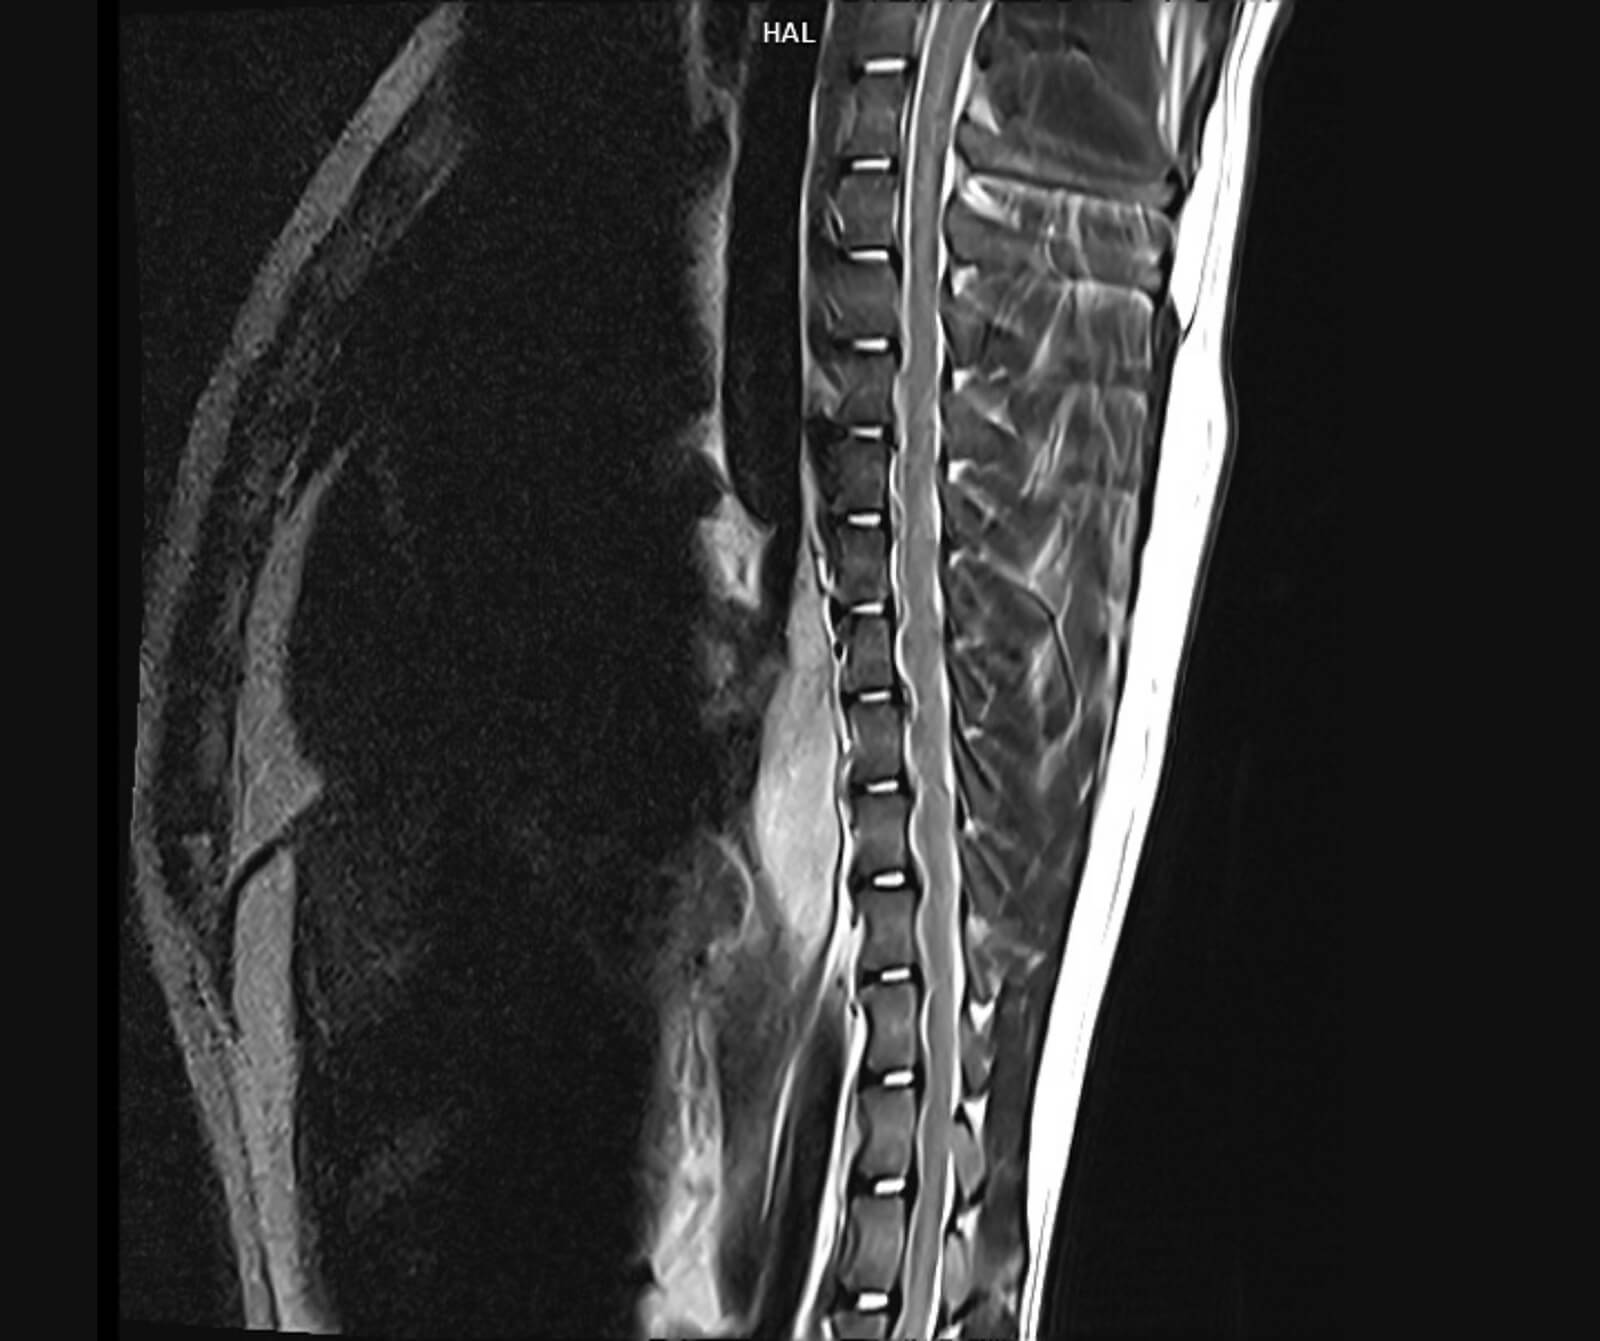

• Spinal kord incelemeleri

• Disk hernisi, omurga tümörleri, enfeksiyonlar ve spinal stenoz

• Omurilikte travmatik ve dejeneratif değişiklikler